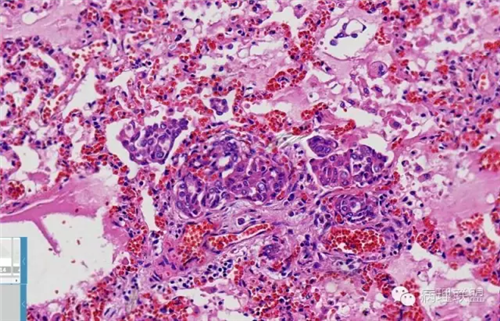

肺的

不仅仅是肺水肿